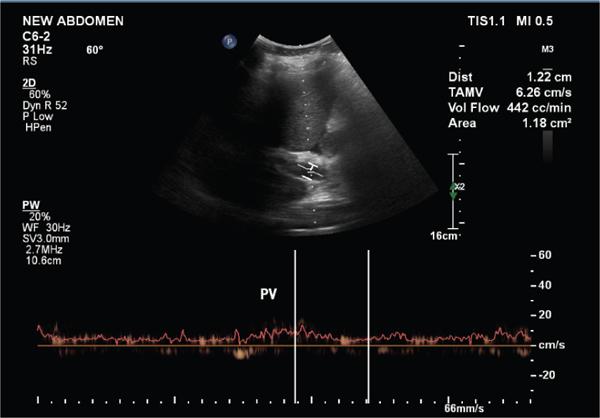

Shrinivas B. Desai, Ritu K. Kashikar, Aman Snehil, Ajay Jhaveri Cirrhosis is a late stage of irreversible scarring of the liver causing abnormality in liver structure and function. Multiple conditions and factors can cause repeated liver damage and scarring ultimately leading to cirrhosis. The most feared complication of liver cirrhosis is the development of hepatocellular carcinoma (HCC). Portal hypertension (PHT) is seen with a variety of conditions but cirrhosis happens to the most important cause. Imaging plays a vital role in noninvasive diagnosis and treatment planning of both cirrhosis and PHT. Liver imaging reporting and data system (LI-RADS) is a standardized reporting system assigning an observation risk of representing HCC. This chapter focuses on discussing aetiologies and imaging of PHT with a lucid review of L1-RADS 2018 version. The portal blood circulation is a unique circulatory circuit as it connects two capillary beds between the liver parenchyma at one end and the gastrointestinal tract and splenic parenchyma at the other end. The portal system ramifies in the liver and ultimately ends in the hepatic sinusoids from where the blood ultimately drains into the inferior vena cava (IVC). The portal vein (PV) originates from the capillary beds in the stomach, intestine and the spleen. The main PV is formed behind the neck of the pancreas by the confluence of the superior mesenteric vein (SMV) and splenic vein. It continues to the porta hepatis where it bifurcates into the left and right branches as it carries nutrient rich but oxygen poor blood to the liver (Fig. 9.9.1). The PV makes up for 75%–80% of the liver’s blood supply while the hepatic artery which arises from the celiac trunk makes up for the remaining 25%. A pathological increase in the portal venous pressure is referred to as PHT. PHT is most often a sequel of chronic parenchymal liver disease and leads to major life-threatening complications due to bleeding from the collateral circulation (most commonly oesophageal varices). Direct measurement of portal pressure (PP) is invasive and often not feasible in most patients and thus imaging plays an important role in the diagnosis of PHT and its complications. The normal portal venous pressure ranges between 5 and 10 mmHg, which is the equivalent of 7–14 cm H2O. The normal hepatic venous pressure gradient (HVPG) is the pressure gradient between the PV and the IVC, is typically 1–5 mmHg. Presence of PHT is indicated by a wedged hepatic venous pressure of more than 5 mmHg. Other definitions include a splenic pressure of more than 15 mmHg or an intraoperative PP of greater than 30 cm H2O. The complications of PHT are seen when HVPG is greater than 10 mmHg and hence this value defines clinically significant PHT. Variceal bleeding is seen with a pressure greater than 12 mmHg. In ideal conditions, the portal circuit is a high flow, low resistance circuit as it has to allow substantial flow rates of 700–1000 mL/min to the hepatic parenchyma from the gastrointestinal tract. Anatomical changes in the organization of the hepatic lobule can result in rise in the portal resistance. These can occur in the form of collagen deposition in the space of Disse, fibrotic scars formed due to regenerative nodule (RN) formation, loss of normal elasticity of the endothelium and distal venous thrombosis. Changes in splanchnic haemodynamics due to factors that increase splanchnic blood flow and increase in intrahepatic vascular resistance due to transformation of stellate cells into myofibroblasts also contribute to the increase in PP gradient. In Western countries, alcoholic cirrhosis and viral cirrhosis are the leading causes of PHT and oesophageal varices. The viral causes form majority of cases leading to cirrhosis and PHT in the Far East and Middle Eastern countries while Schistosomiasis remains an important cause in the African countries. Worldwide, nonalcoholic steatohepatitis (NASH) and hepatitis C are the emerging causes of chronic liver disease (CLD) and PHT. PHT can be classified as cirrhotic and noncirrhotic depending on whether it is associated with cirrhosis or not. This distinction is important as noncirrhotic causes like PV thrombosis are at high risk of development of bleeding but tend to have a better chance of surviving a variceal bleed than a patient with decompensated alcoholic cirrhosis due to preserved hepatic synthetic functions in the former. PHT can also be classified on the basis of the location of the pathology into prehepatic, hepatic and posthepatic causes. Hepatic causes can further be divided into presinusoidal, sinusoidal and postsinusoidal. The causes of portal hypertension have been denoted in Table 9.9.1. The direct measurement of the PP by measuring the HVPG is invasive, expensive not readily available in all patients. Thus, imaging plays an important role in the diagnosis of PHT. Various modalities are used for the imaging diagnosis of PHT. Ultrasonography (USG) and Doppler evaluation have the advantage of being inexpensive, readily available and bedside modality (Table 9.9.2). The role of ultrasound and Doppler in imaging of PHT is to: Grey scale imaging is useful in evaluating the splenoportal anatomy. The evaluation should begin with the liver morphology. Signs of cirrhosis like nodularity of the liver surface with relative atrophy of the right lobe and prominence of the left lobe and caudate should be looked for. Hepatic echotexture appears coarse and more echogenic (Table 9.9.3). Increase in portal venous diameter is a sign of PHT (Fig. 9.9.2). Portal venous diameter of more than 13 or 15 mm has low sensitivity for diagnosing PHT of only 40%–12.5%, respectively. Absolute measurement of the portal diameter as a sign of PHT is also fallacious as in presence of collateral circulation or hepatofugal flow; there may actually be a decrease in the PV diameter. Therefore, a more accurate sign is respiratory variation of PV diameter. An increase in PV diameter of less than 20% with deep inspiration has been reported to indicate PHT with a sensitivity of 80% and specificity of 100%. This has been reported to be an accurate indicator of cirrhosis. Hepatic vein straightness, uniformity of vein wall echogenicity and visualization of at least 1 cm segment of the hepatic vein are the parameters used for evaluation. Splenomegaly is defined as bipolar splenic diameter of greater than 12 cm or largest splenic cross-sectional area passing through the hilum of greater than 45 cm2, and occurs secondary to PHT (Fig. 9.9.3). A total of 65%–80% patients with cirrhosis have splenomegaly on ultrasound. Patients with cirrhosis due to viral hepatitis and primary biliary cirrhosis show splenomegaly more frequently than those with alcoholic cirrhosis. This is an accurate sign of PHT. USG is extremely sensitive with respect to detecting subclinical ascites. Perihepatic space is the most usual site of visualization of minimal ascites. In normal subjects, this ratio is approximately 0.07 and a value above 0.1 suggests the diagnosis of PHT with a 95% sensitivity and specificity. The normal spectral waveform of the hepatic artery is a low resistance flow pattern with forward flow in diastole and a resistivity index in the range of 0.5–0.7. In PHT, the resistivity index of the hepatic artery increases with high resistance flow pattern due to increased peripheral vascular resistance. Resistance index (RI) > 0.78 in the intrahepatic branches of the hepatic artery has been reported to have a sensitivity of 50% and a specificity of 100% for the detection of PHT (Fig. 9.9.11). Pulsatility index (PI) > 1.05 suggests severe PHT with a sensitivity of 86% and specificity of 88% (Fig. 9.9.11). Patency of hepatic veins should be evaluated to rule out Budd–Chiari syndrome as a cause of PHT. The normal hepatic venous waveform (HVW) reflects right atrial activity and this results in a triphasic waveform with one positive and two negative waves. In PHT, this waveform becomes monophasic or biphasic. A monophasic HVW has a sensitivity and specificity of 74% and 95%, respectively, in the diagnosis of severe PHT (Fig. 9.9.12). Dilatation of the splanchnic veins – the SMV and the splenic vein – more than 11 mm are suggestive of PHT with a sensitivity and specificity of 72% and 100%, respectively. A reduction in the respiratory variation of the splenic vein and SMV to less than 40% had a sensitivity and specificity of 79.7% and 100%, respectively, for the diagnosis of PHT (Fig. 9.9.13). The splenic artery reveals an increase in the resistivity index and an RI of >0.63 and a PI of >1 have a sensitivity and specificity of 84.6% and 70.4% for the diagnosis of PHT. Presence of portosystemic collaterals like patent paraumbilical vein, dilated left gastric and short gastric veins are 100% specific sign for PHT (Figs. 9.9.14–9.9.16). Recanalization of the paraumbilical vein, known as the Cruveilhier–Baumgarten syndrome is observed in 43% of patients with PHT, and this is the easiest collateral to assess during the US examination. Various portosystemic collaterals that occur in PHT have been discussed in details in subsection on CT findings in PHT. No Doppler parameter is considered reliable enough to measure PP with sufficient accuracy for use in clinical practice. Oesophageal varices are often present in patients with portosystemic collaterals. Appearance or increase in number of collaterals along with splenomegaly has a high association with variceal formation and growth. USG helps in diagnosis of prehepatic causes like portal stenosis or thrombosis by demonstrating the patency and morphology of the splenoportal system. Arteriovenous fistulae and tumours causing vascular thrombosis as aetiology can be readily detected. USG helps in diagnosis of features of cirrhosis and thus helps differentiate noncirrhotic causes of PHT. USG allows diagnosis of fatty liver disease, which is an emerging cause of cirrhosis. Among the posthepatic causes, USG aids in establishing the diagnosis of Budd–Chiari syndrome by demonstrating the patency and morphology of the IVC and hepatic veins. Owing to the inability of CT to detect flow direction, portal flow rates or pressure gradients, CT is not the primary modality in diagnosis of PHT. Similar to USG dilatation of portosystemic system is a feature of PHT (Fig. 9.9.17). Changes in cirrhosis if present can be seen in the form of surface nodularity, nodules and fibrous septae. CT plays an important role in diagnosis of portal venous thrombosis and evaluating its extent. An acute thrombus is seen as a hypodense filling defect in the vessel causing distension of the venous lumen. Surrounding fat stranding can be seen. A chronic thrombus appears as an eccentric filling defect usually along the wall and is often associated with decrease in vessel diameter. Calcification may be seen in chronic thrombi. Multidetector computed tomography (MDCT) is a useful tool to evaluate portosystemic collateral circulation and recognize complications of PHT. 3D angiography can help understand portal venous and complex variceal anatomy and plan treatment. The various portosystemic collaterals are discussed below. They can be classified into those draining into superior vena cava (SVC) and those draining into the IVC. Magnetic resonance imaging (MRI) is a noninvasive modality used in the evaluation of PHT without the use of ionising radiation. It provides evaluation of parenchymal abnormalities, collaterals and characterization of tumours (Fig. 9.9.28). Spin echo sequences allow characterization of liver masses and liver parenchyma. Loss of flow void allows for detection of thrombosis. Time-of-flight (TOF) angiography is useful in assessing the portal venous system and allows for successful detection of PV thrombosis. The disadvantages of TOF are motion artefacts caused by breathing, long acquisition times and incomplete coverage of the portal venous system. Novel imaging techniques include phase contrast, T1 mapping and magnetic resonance elastography (MRE). The advantage of phase contrast over TOF imaging is that phase contrast imaging acquires information regarding the flow direction in addition to the information regarding the flow velocity. On-phase contrast images signal within vessel is hyperintense when flow is cranial and hypointense when flow is caudal. Look-Locker imaging technique using gradient echo (GRE) MRI sequences with inversion recovery pulse is used to quantify fibrosis by measuring precontrast T1 relaxation times. Interventions in PHT can be aimed at diagnosis or more commonly at management of complications of PHT. HVPG measurement, which is the gold standard for the diagnosis of PHT, can be achieved through cannulation of the PV. Transjugular hepatic biopsy is another diagnostic invasive technique that also allows indirect measurement of PP. Disadvantages include deterioration of hepatic function caused by diversion of portal venous blood flow and shunt dysfunction. TIPSS is contraindicated in patients with congestive heart failure, severe pulmonary hypertension, severe tricuspid regurgitation and hepatic failure. In this technique, a catheter is advanced from the femoral vein into the outlet of the gastrorenal, usually in the region of the left renal vein. The shunt is then occluded with a balloon and sclerosant is injected retrograde to occlude the gastric varices. Histological development of RNs surrounded by fibrous septae in response to chronic liver injury, progressing PHT and end-stage liver disease is termed as cirrhosis. Although initially considered an end-stage phenomenon in CLD, recent evidence suggests that the histological fibrosis can be reversible in early stages with the initiation of specific therapies, for example, in viral cirrhosis with the initiation of antiviral therapy. The one-year mortality rate in cirrhosis varies widely from 1% to 57% depending on the occurrence of complications. Cirrhosis can have a wide variety of causes ranging from congenital to acquired and infectious to noninfectious. It is also a major aetiologic risk factor for the development of HCC. Imaging plays an important role in aetiologic diagnosis of this diverse entity as well as in the diagnosis and management of its complication and surveillance for oncological transformation.

A. Portal vein